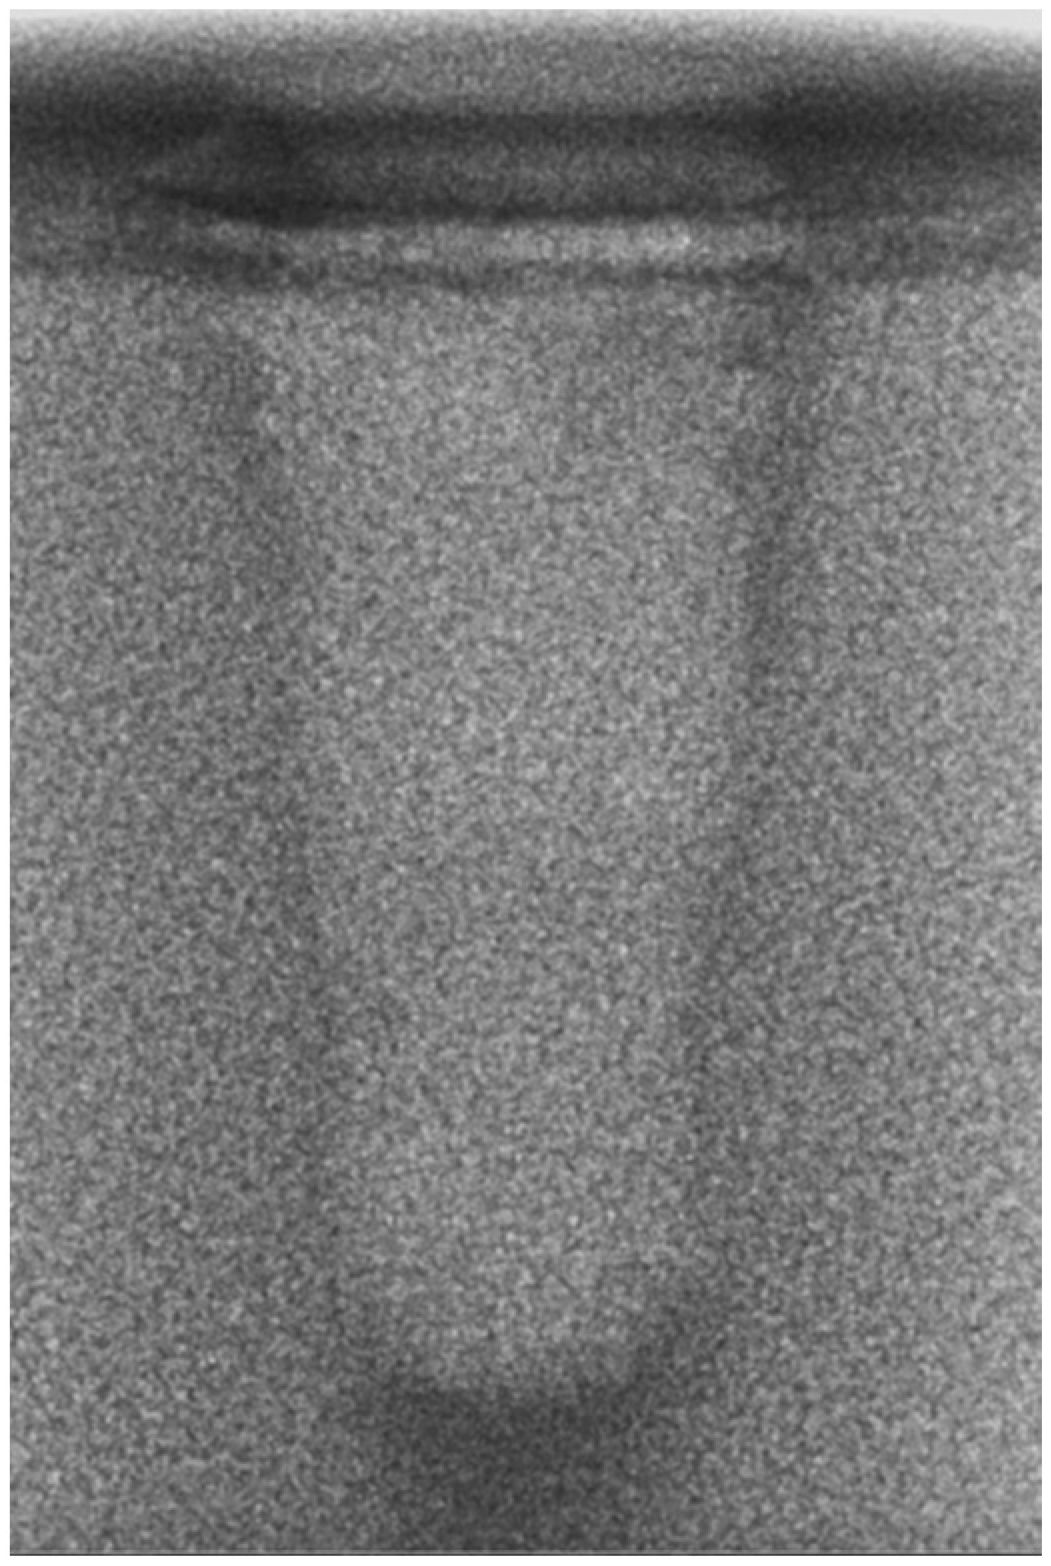

- Vertical effect of magnetic mallet: The forces produced by the MM are transmitted to the tip of the osteotome in order to achieve the plastic deformation of the bone. These forces can affect the bone in three dimensions: horizontally, vertically, and sagittally. However, the vertical effect of the MM goes beyond the area that is in direct contact with the instrument’s tip. By employing a Micro-CT scan, we accurately measured the extent of condensed bone located apically to the preparation site. The results indicate a direct correlation between the size of the condensed area and the density of the bone. Figure 3 shows an implant prepared site employing the MM technique in a bone density of 30 PCF. The length of our preparation measured 11 mm, while the condensed bone resulting from osteotomy extended 3.7 ± 0.14 mm apically to the implant site preparation. By comparing the MM with the other preparation techniques in the same bone density, we observed that, in the sites prepared using the PES approach, the vertical effect of the preparation was noticeably less than that of the MM. It extended apically to the implant site preparation at 0.36 ± 0.08 mm, as shown in Figure 4. When employing the TD technique, we noticed that the vertical effect of this preparation method was minimal compared to the MM and PES, measuring 0.15 ± 0.04 mm, as shown in Figure 5.